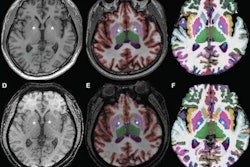

BoneMRI generates 3D MRI images aimed at enhancing visualization of bone structures. Image courtesy of MRIguidance.

BoneMRI generates 3D MRI images aimed at enhancing visualization of bone structures. Image courtesy of MRIguidance.The FDA clearance covers the use of the software in the pelvic region, including the bony anatomy of the sacrum, hip bones, and femoral heads. The company said it also intends to extend the clearance to include the spine later this year.